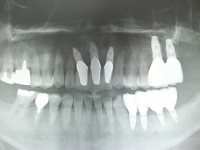

臼歯部、前歯部共にスプリットクレスト、GBRしての埋入でしたね。

この様な前歯部欠損の場合で臼歯部での垂直的な咬合が崩壊してしまっている場合は、まず臼歯部からの咬合の再構築を優先させなければいけません、前歯部歯牙は臼歯部でのしっかりとした垂直的な噛みあわせがあるからこそ守られているという事を認識しておく必要がありますね。!